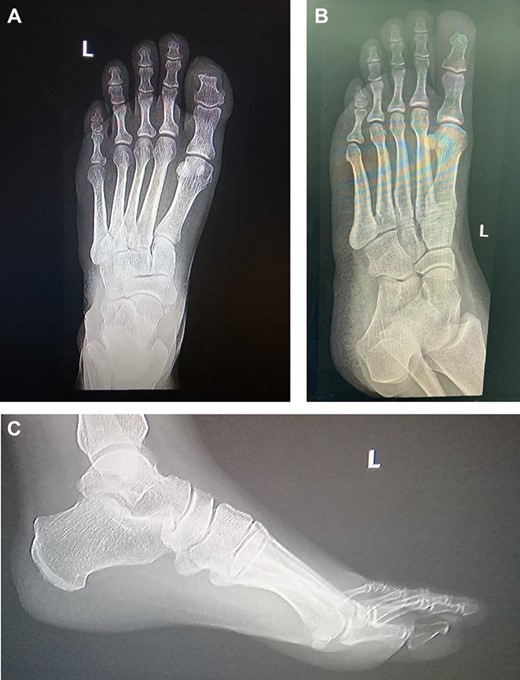

The patient was then referred to the infectious disease team, and a 6-week course of clindamycin was started to eradicate the infection. Follow up after 19 months shows no recurrence (Figs 4 and 5).

19 months post excision and coverage with Kutler bilateral V-Y advancement flaps with no evidence of recurrence.

Left foot X-ray 19 months post excision and coverage with Kutler bilateral V-Y advancement flaps no evidence of recurrence.